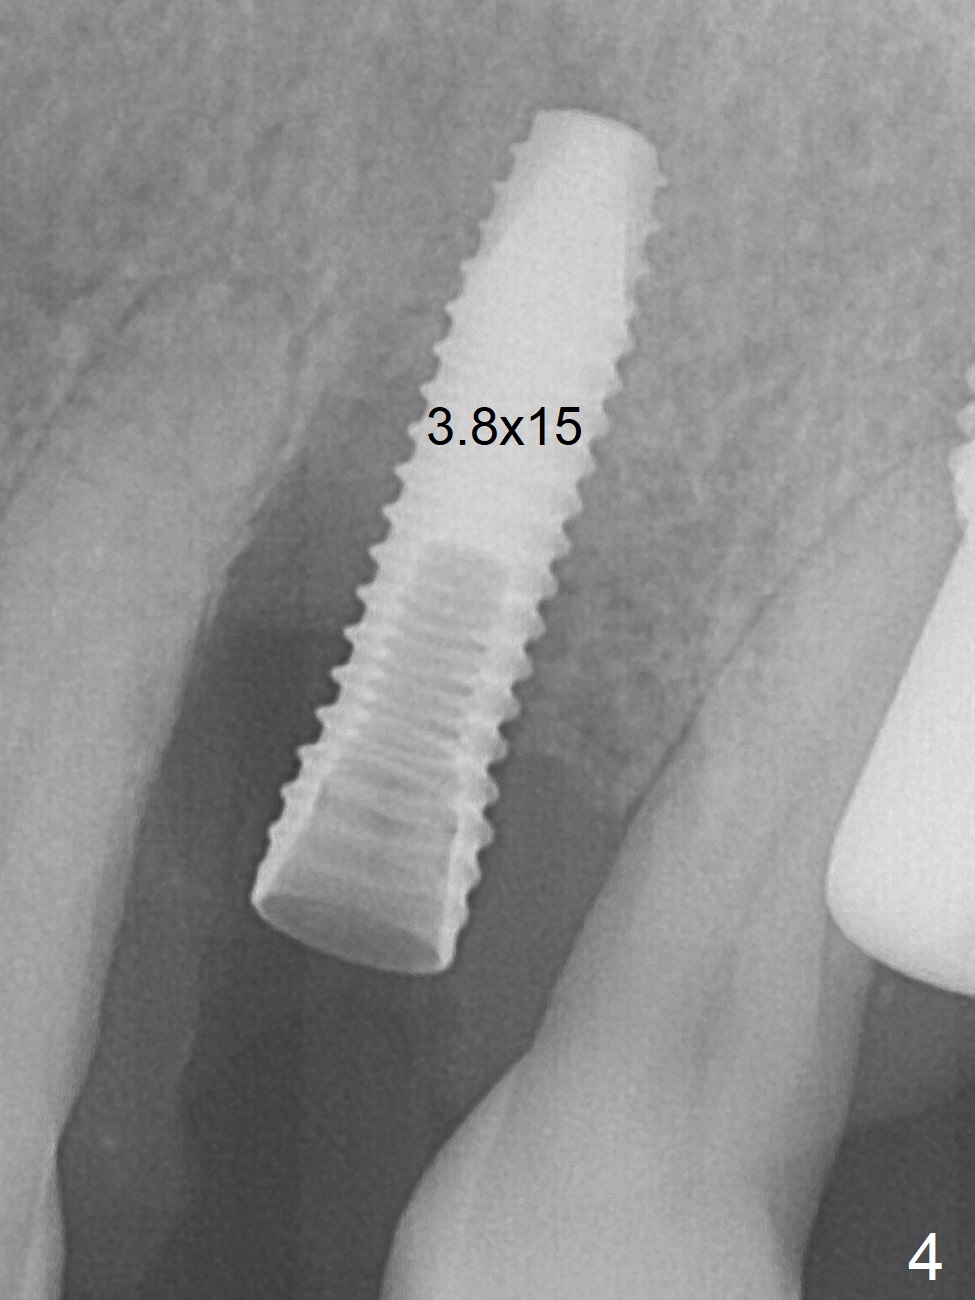

A few days prior to surgery, the tooth #12 developed abscess, self controlled by water pik (Fig.1 *). The buccal plate is defective. Initial osteotomy is close to the root of the tooth #11 (Fig.2). After adjustment of the trajectory and the depth of osteotomy (Fig.3), a 3.8x15 mm dummy implant is placed (Fig.4,5). In spite of a shorter implant (3.8x13 mm) placed deeper, approximately 7 mm implant threads are not covered buccally by the native bone (Fig.6 red dashed line). If the implant were placed deeper, the crown/implant ratio would become more unfavorable (abutment screw loosening, Fig.7). Since a mill abutment (4.5(2) mm) is inserted before Vanilla Graft, the deepest portion of the socket is unfilled (Fig.7 *). With meticulous use of a long explorer and additional allograft, the space is closed (Fig.8 *). The buccal plate collapses with apparently fistula formation 2 months postop. The patient removes the provisional for cleaning. It appears that the mill abutment is buccally placed and needs heavy reduction. The mill abutment is loose 2 months 10 days postop. When it is retightened, it tilts distal. Bone remains around the implant 6 months postop (Fig.9). Without a provisional at #12 for 5 months, the tooth #13 appears to have been shifted mesially (Fig.10 arrow). The mill abutment at #12 changes to a healing one. A lingual button is placed in the mesial surface of #13. Splinted provisional is fabricated with supraocclusion at #14 and 15 as an anchor (implants). The tooth #13 is being distalized with power chains. Limited ortho is finished nearly 2 months post banding (Fig.15,16).